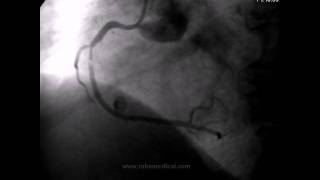

Cateterismo Cardiaco.

Cateterismo cardiaco Es un estudio diagnostico y terapéutico con lo que se logra conocer la enfermedad cardiaca así como su resolución en...